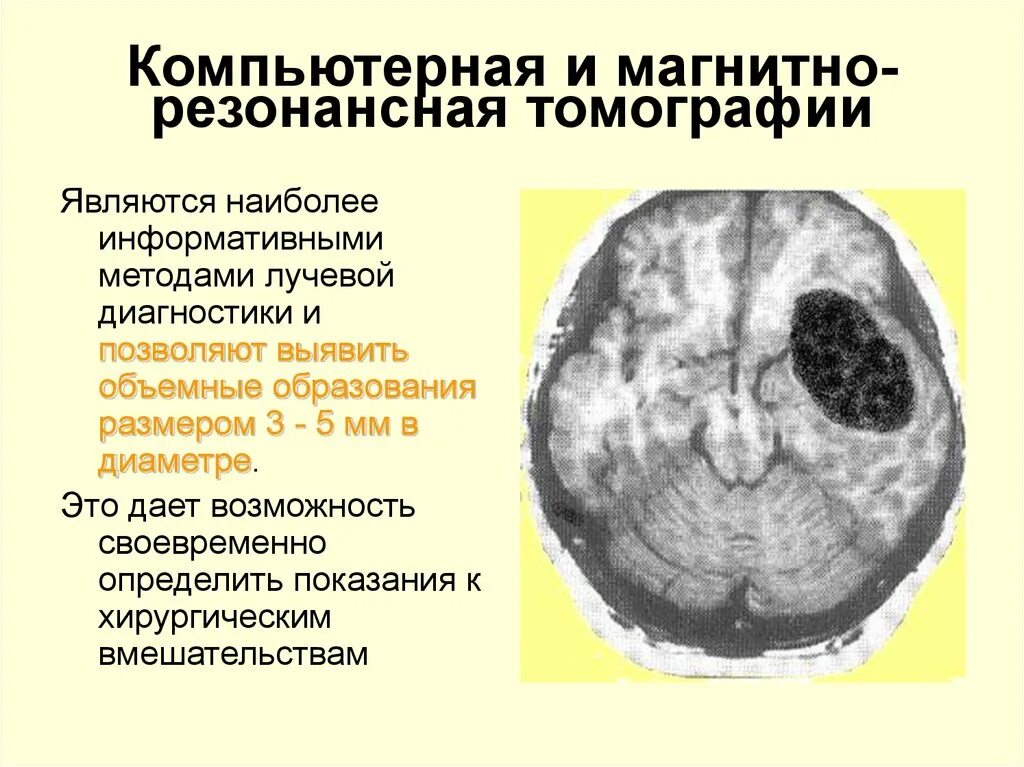

Опухоль головного мозга стадии. Опухоль головного мозга симптомы. Проявление опухоли головного мозга. Степени опухолей головного мозга. Методы исследования при опухоли головного мозга. Дополнительные методы исследования опухолей головного мозга. Диагноз кт с опухолью головного мозга. Дополнительные методы исследования при опухолях головного мозга.

Методы исследования при опухоли головного мозга. Дополнительные методы исследования опухолей головного мозга. Диагноз кт с опухолью головного мозга. Дополнительные методы исследования при опухолях головного мозга. Диагностика ра а желудка. РВК желудка дипгностика. Иагностика рада желудка. Методы диагностики в онкологии.